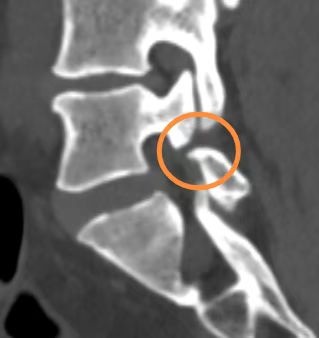

杨女士,30 岁,因长期久坐且健身方式不当(频繁进行硬拉锻炼),两年前开始出现腰痛和左腿痛。当时于我院脊柱外科蒋帅副主任医师处就诊,诊断为“腰椎间盘突出症、腰5峡部裂”,症状较轻,采取保守治疗后有所好转,但腰痛仍时有反复且逐渐加重。上个月劳累后,左腿出现放射状疼痛,输液治疗后虽有缓解,但左腿麻木严重。再次就诊后,腰椎磁共振显示椎间盘脱出并向下游离,CT显示L5椎弓根峡部断裂,X片提示腰椎不稳,经详细检查,确诊为:L4/5 巨大腰椎间盘脱出和L5 双侧腰椎峡部裂。

这两种疾病同时存在,使她的腰痛和腿痛症状雪上加霜,患者L4/5巨大的腰椎间盘脱出严重压迫了神经根,需手术干预,否则神经受压时间过长会造成更严重的神经损伤。患者腰椎峡部裂导致腰椎不稳,腰5/骶1的椎间盘变性,腰痛逐年加重,也需手术处理,否则病情会逐渐加重。

术后3天:复查腰椎CT+MRI显示神经压迫完全解除,内固定位置良好,腰痛和腿痛较术前明显好转。